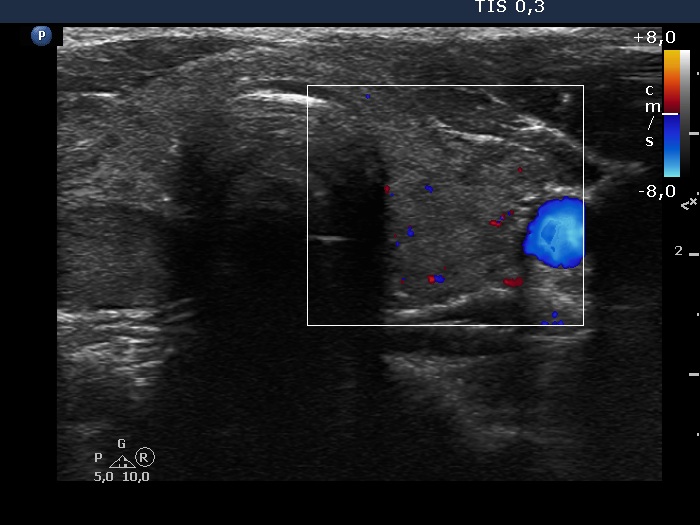

Graves' disease - case 572

Follow-up examination 6 years after the first visit (ultrasonographic picture 6)

Left lobe, transverse scan, color Doppler mode. The vascularization is very scanty.